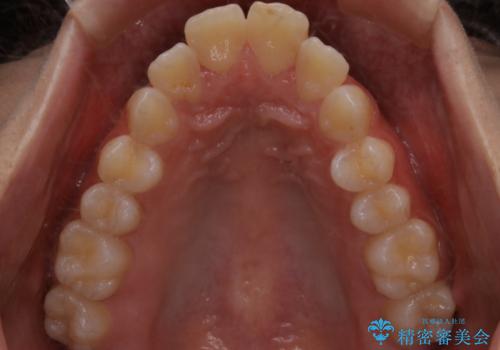

- 出っ歯が気になるとご相談にいらした方です。抜歯して歯を並べました。深かった噛み合わせも改善させることが出来ました。

噛み合わせが元々深い方は一般的に噛む力が強く、治療に時間がかかる傾向にあります。治療前の想定よりも短期間でスムーズに治療を終える事ができ、大変喜んでいただけました。リテーナーによる保定もしっかり行っていただいており、後戻りなく快適にすごして頂けているとのことです。